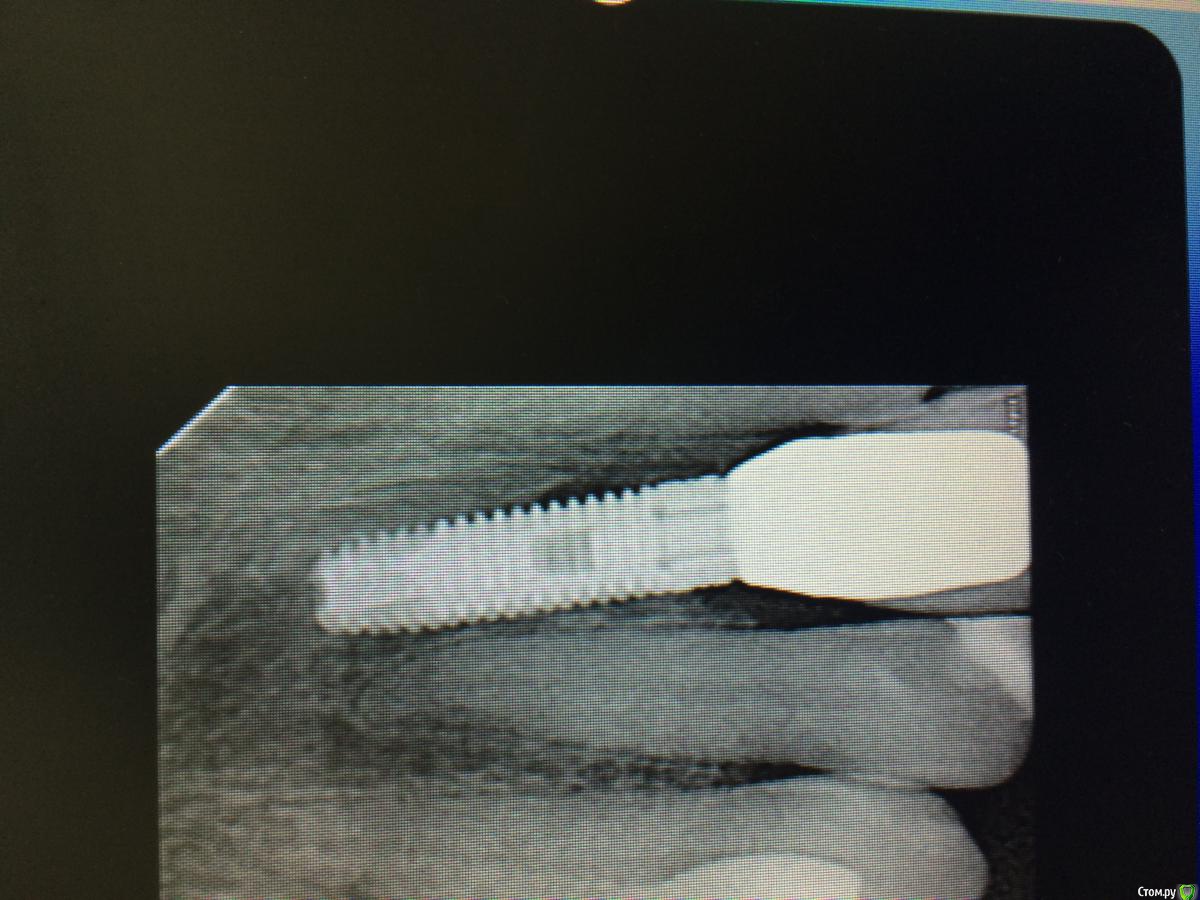

K.E. Опубликовано 27 февраля, 2016 Автор Поделиться Опубликовано 27 февраля, 2016 Ситуация на данный момент. Снимок рентгена сделан с экрана монитора. 5 Ссылка на комментарий